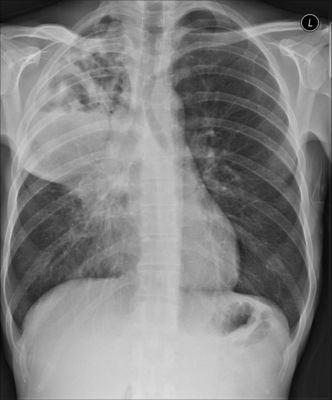

Paciente de 45 anos, diabético, hipertenso e com diagnóstico de bronquite crônica e bronquiectasias em pulmão direito, com tosse produtiva ha 5 anos, apresentando há dois meses febre baixa, piora da dispneia, alteração da purulência e quantidade de escarro, que agora tem odor extremamente pútrido. Sua radiografia de tórax é mostrada abaixo. A baciloscopia de escarro e o PCR para BK foram negativos A melhor opção antibiótica inicial, dentre as abaixo é:

Answer

• Ampicilina + sulbactan

• Clindamicina

• Piperacilina + tazobactan

• Cefepime